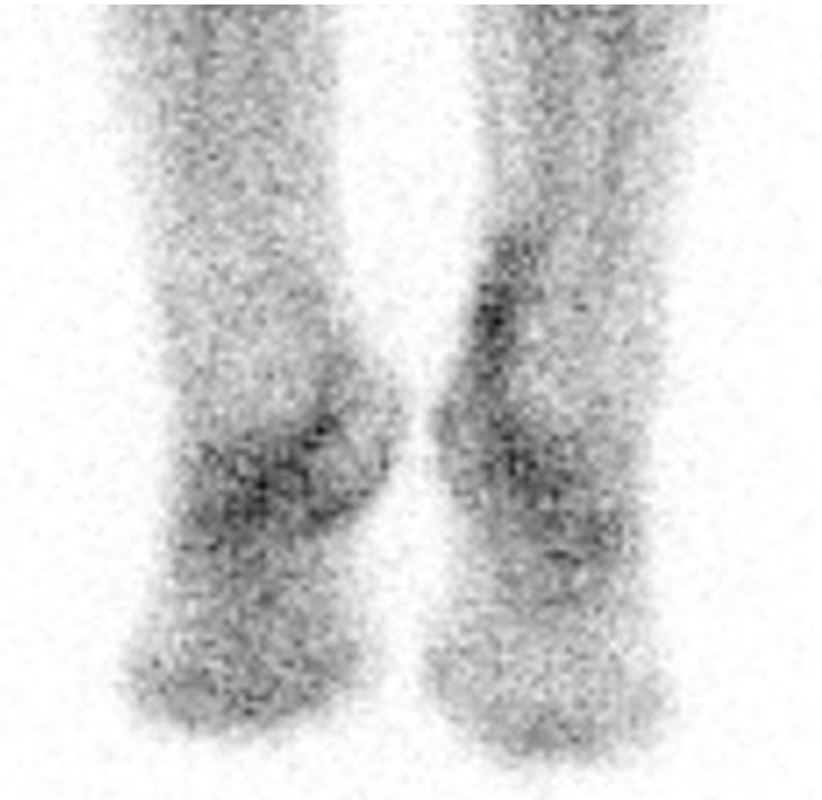

Der Vorteil der Methode liegt in der Kombination einer sensitiven Detektion eines pathologisch gesteigerten Knochen­stoffwechsels und einer sehr hohen CT-morphologischen Ortsauflösung im Submillimeterbereich (0,6 mm) in einer anatomisch komplexen und variantenreichen Körperregion. Damit ergibt sich eine präzise Bildqualität wie sie für eine chirurgische Therapie­planung ideal ist. Dabei werden immer beide Füße und Sprunggelenke parallel dargestellt, so dass auch Seitenvergleiche die Zuordnung von bestimmten Veränderungen erleichtern können. Die Schnittebenen können im Gegensatz zur MRT auch nach Abschluss der Untersuchung frei gewählt und so Pathologien optimal herausgearbeitet und präsentiert werden.